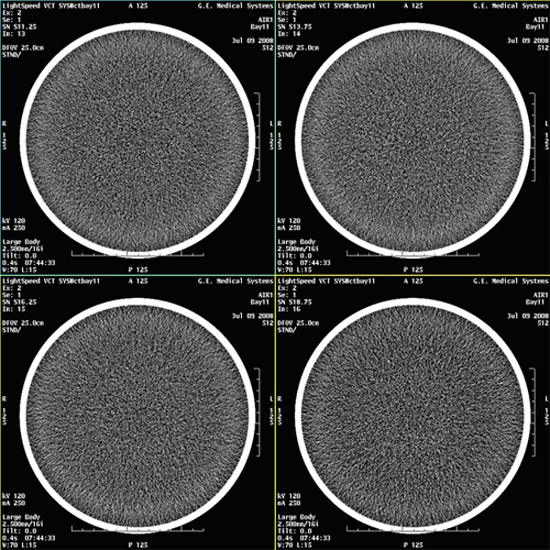

- Select VIEWER and review all images for

blotchy artifacts. (See Figure 1, Figure 2, and Figure 3). If an artifact is encountered, perform Tube Oil Cooling System Air Removal.note:

If air artifact exists, the air activity may be more significant in Images 13 through 16, 29 through 32, 45 through 48, and 61 through 64.

Figure 1. Images with No Air Artifacts